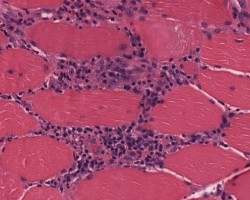

- Muscle biopsy shows perifascicular inflammation and atrophy with sparing of the central fascicle.